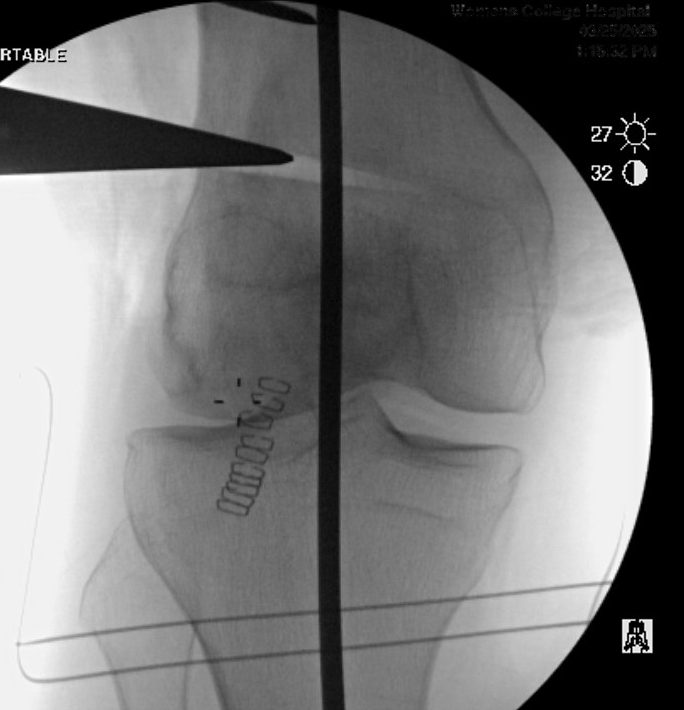

Preoperative Planning

AP full length standing xrays

Line from centre of talus to desired mechanical axis

Line from centre of femoral head to desired mechanical axis

a) is the desired angle of correction

Valgus OA Preop PlanningDFVO preopDistal Femoral Osteotomy Postop View